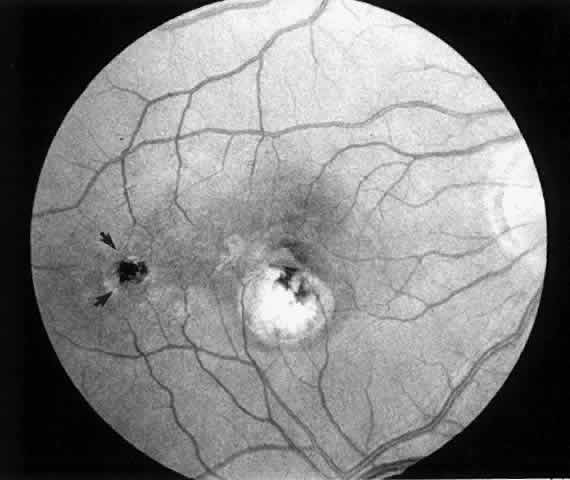

2. A 35-year-old patient developed an idiopathic subfoveal choroidal neovascular membrane with decrease in vision to 20/200 (6/60) (Fig. 9). He underwent surgical excision of the membrane. Laser was applied to the retinotomy at the conclusion of the case. One year after surgery, his visual acuity remained stable at 20/20 (6/6) (Fig. 10).

Fig. 10. Postoperative fundus photograph (case 2). One year after surgery, visual acuity is 20/20 (6/6). Note laser scar at retinotomy site (arrows).